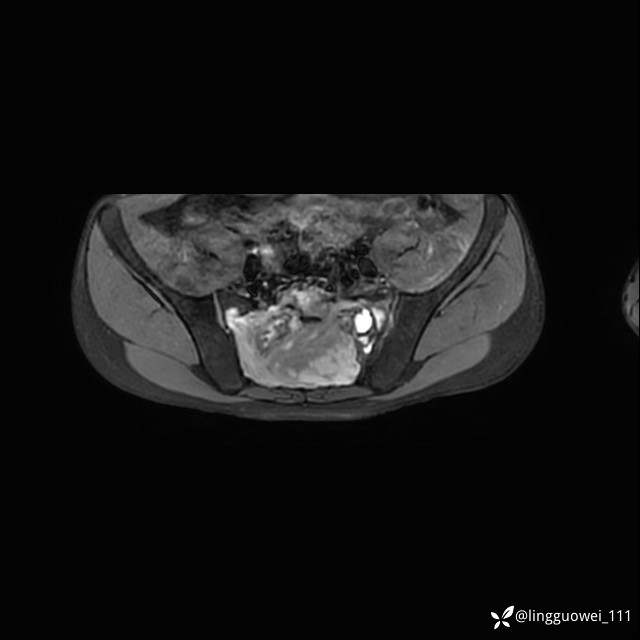

MR:(忘记截图常规序列,不过应该不影响诊断)

img